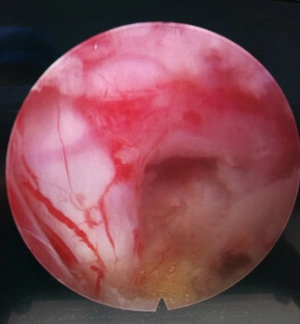

手术充分减压

1.创伤小:该手术不破坏正常的组织结构,对人体影响较小,切口仅1cm左右,出血少,且基本不破坏颈椎的骨性结构,直接摘除病变的椎间盘及黄韧带等结构,精准的进行神经根减压,局部麻醉,术后第二天便可下地行走。

2.效果佳:精准地对压迫物进行摘除,术后患者可短期内感觉症状缓解,大小便自理,护理简单。